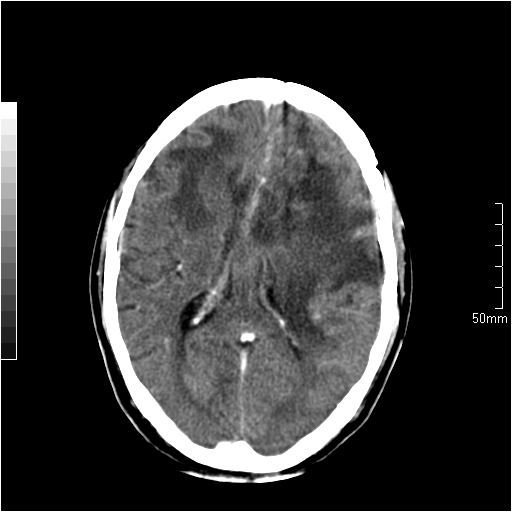

以下是引用天南地北在2007-6-25 12:39:00的发言:[br]有占位效应[br]支持术后复发

以下是引用zjzjr在2007-6-25 12:38:00的发言:[br]左侧复发,右侧转移。